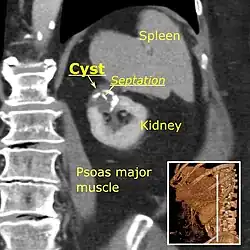

Bosniak II cyst at the lower pole of right kidney with septations within.

The complex cyst can be further evaluated with doppler ultrasonography, and for Bosniak classification and follow-up of complex cysts, either contrast-enhanced ultrasound (CEUS) or contrast CT is used.[13]

Renal ultrasonography of a simple renal cyst with posterior enhancement. -